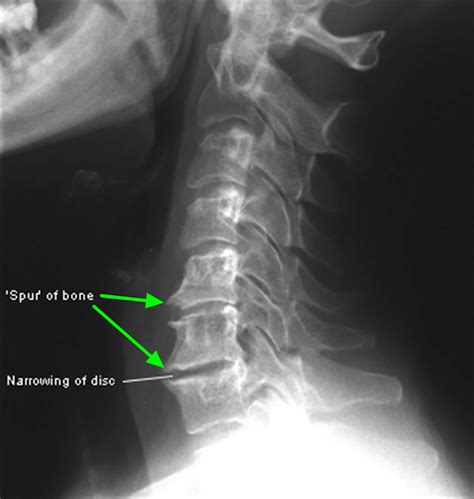

A bone spur is a bony projection that develops along bone edges. In the shoulder, bone spurs can form on the acromion (the highest point of the shoulder blade), the humerus (upper arm bone), or the clavicle (collarbone). These spurs can cause pain and limit shoulder movement, especially when they rub against tendons, ligaments, or other bones.

• Imaging Tests: Diagnostic imaging tests, such as X-rays, CT scans, or MRI scans, can help visualize the bone spur and assess the extent of the damage. These tests provide detailed images of the shoulder joint and surrounding tissues.

X-ray Uses radiation to produce images of the bones. Identify bone spurs and assess bone structure.